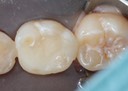

Scott Kanamori #12 finish

Scott Kanamori #12 buccal view